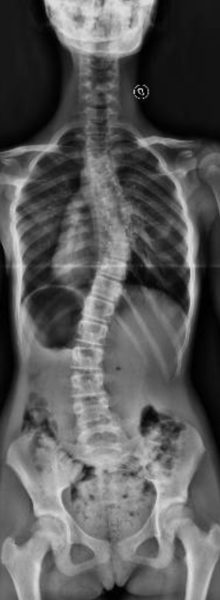

Escoliosis Idiopática del Adolescente.

Tratamiento: Uso de un corsé, y ejercicios indicados para prevenir la progresión de la curvatura. Al año: la escoliosis y el valor angular empeoraron significativamente En la primavera del 2020, plena pandemia, se llevó a cabo la corrección quirúrgica. Hoy, Morena ha logrado retomar sus actividades y actualmente juega al hockey. Su evolución refleja cómo, a pesar de las dificultades, se puede avanzar en el tratamiento de la escoliosis.